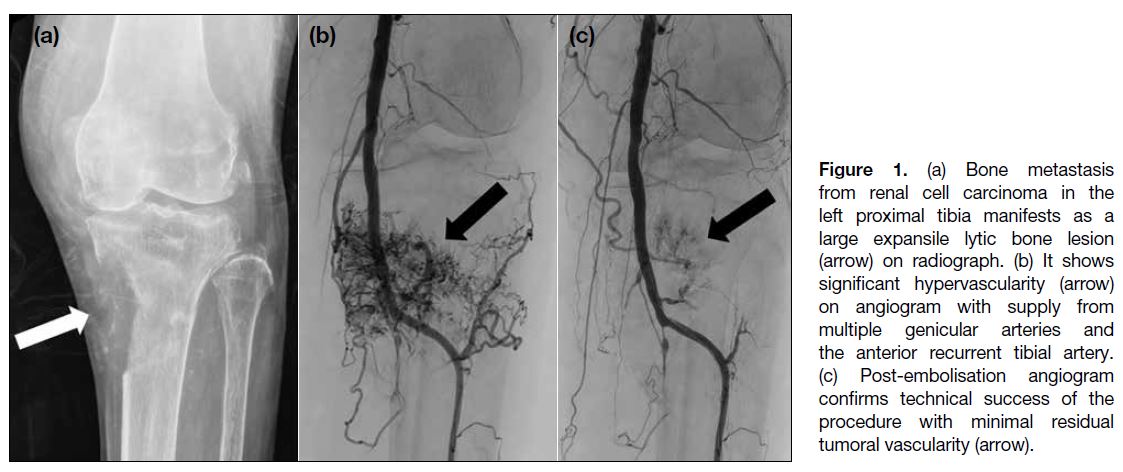

were recorded. The technical success of embolisation,

defined as reduction of tumour arterial blush by ≥70%

on postoperative angiography,[1] [2] as shown in our case (Figure 1), was assessed. In cases of no definite tumoural

Figure 1. (a) Bone metastasis from renal cell carcinoma in the left proximal tibia manifests as a large expansile lytic bone lesion (arrow) on radiograph. (b) It shows significant hypervascularity (arrow) on angiogram with supply from multiple genicular arteries and the anterior recurrent tibial artery. (c) Post-embolisation angiogram confirms technical success of the procedure with minimal residual tumoral vascularity (arrow).